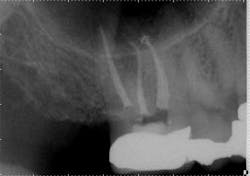

However, when the anatomy is the most complicated with multiple curves or the smallest canals, a different file system might be a better choice (Figs. 3 and 4). Although almost all root canals can be treated with WaveOne, in certain anatomies the root canal procedure is actually easier and more efficient when utilizing a file system that has more tip sizes and taper choices and ultimately requires more files. Vortex Blue (Dentsply Tulsa Dental Specialties), with its incredible resistance to cyclic fatigue and reduced shape memory, is an ideal file choice in this clinical situation. Vortex Blue files have tip sizes ranging from ISO 15-50 and tapers of 0.04 and 0.06. This results in great flexibility to treat the most complicated canal anatomies — flexibility not only in the file itself, but also in the size and taper choices that are available. However, to appreciate the metallurgical advantages of the Vortex Blue files, it may be necessary to spin four or as many as six files per canal.

Fig. 3: Preoperative anatomy of tooth No. 31 shows a double curve in the mesial root canal. The size, length and taper of the root suggest a file system with multiple tip and taper choices would be most suitable.

Fig. 4: A glide path was established with a 15/0.04 Vortex Blue rotary file in conjunction with size 10 hand files. Vortex Blue files were then used in sequence until a final shape of 30/0.04 was achieved in the mesial root and 30/0.06 in the distal root.